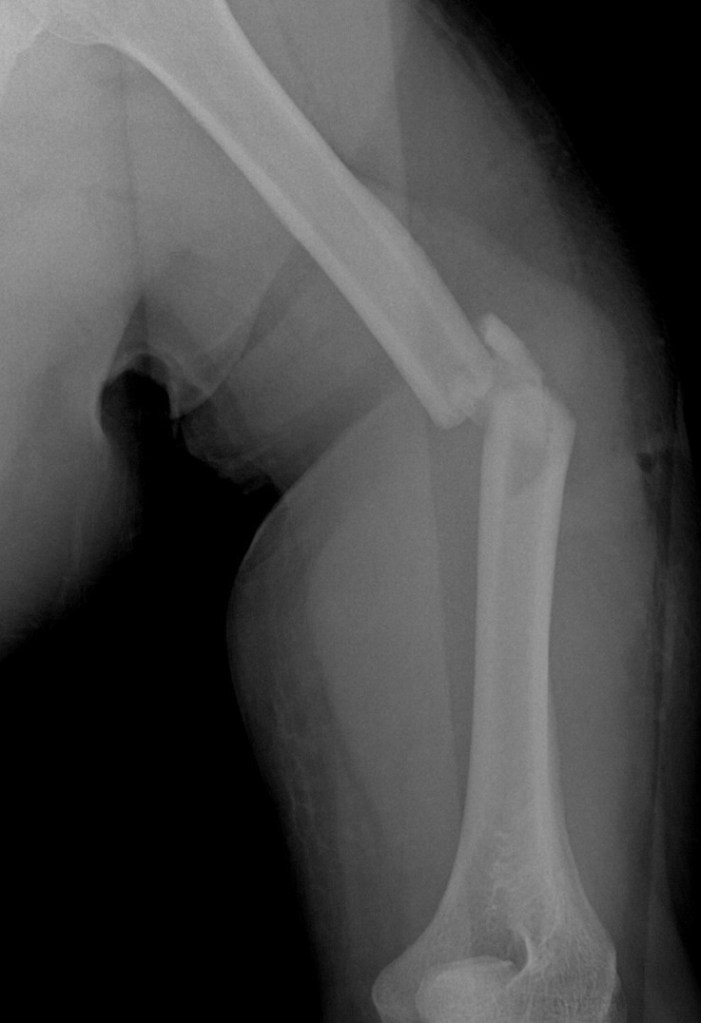

“Pak, ini hasil CT Scan dan rontgen yang pagi tadi,” kata sang dokter jaga menunjukkan file yang ada di handphone-nya. “Semua ok, ada 13 file, nanti saya kirimkan ke hape Bapak.”

“Pada dasarnya semua ok. Kecuali humerus, lengan atas kiri yang harus dioperasi. Kita bisa jadwalkan operasi di sini, besok jam satu siang. Tapi kalau Bapak punya pertimbangan lain kita bisa bikin rujukan.”